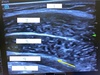

what indicates an appropriately placed TAP block on US?

separation of the plane between internal oblique and TA muscle

what are these things if your US probe is on a tummy

1. Subq 2. external oblique 3. internal oblique 4. transversus abdominus 5. abdominal content